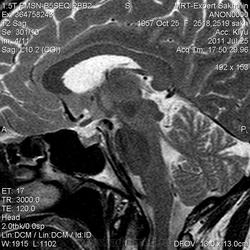

Женщина.6 лет назад выявлено образование левой доли нейрогипофиза.Пришла на контроль.

Постконтраст

Мне самой показался случай не совсем ясным, но динамик четко показывает участок с отставанием в контрастировании, воронка смещена вправо-о чем  думать бедному начинающему специалисту?